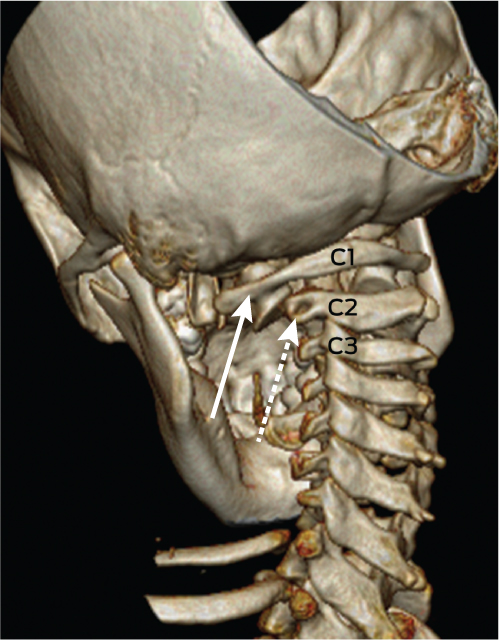

On Day 11, in view of ongoing neck pain and torticollis, a computed tomography (CT) scan of the patient’s neck showed rotational atlantoaxial subluxation, with C1 rotated to the right relative to C2, and persistent bilateral cervical lymphadenopathy (Box 1 and Box 2). The other feature on the CT scan was a hypodense region in the retropharyngeal area measuring 6 mm anteroposteriorly and 7.6 mm mediolaterally, possibly indicating a retropharyngeal abscess (Box 3). Intravenous cefotaxime and lincomycin were therefore continued for 14 days. The patient was placed in cervical traction for 8 days to reduce the subluxation, followed by visor orthosis (a rigid vest and collar) to immobilise her neck.

1 Three-dimensional reconstruction of a computed tomography scan showing the left lateral mass of C1 (solid arrow) with subluxation relative to the lateral mass of C2 (dashed arrow)